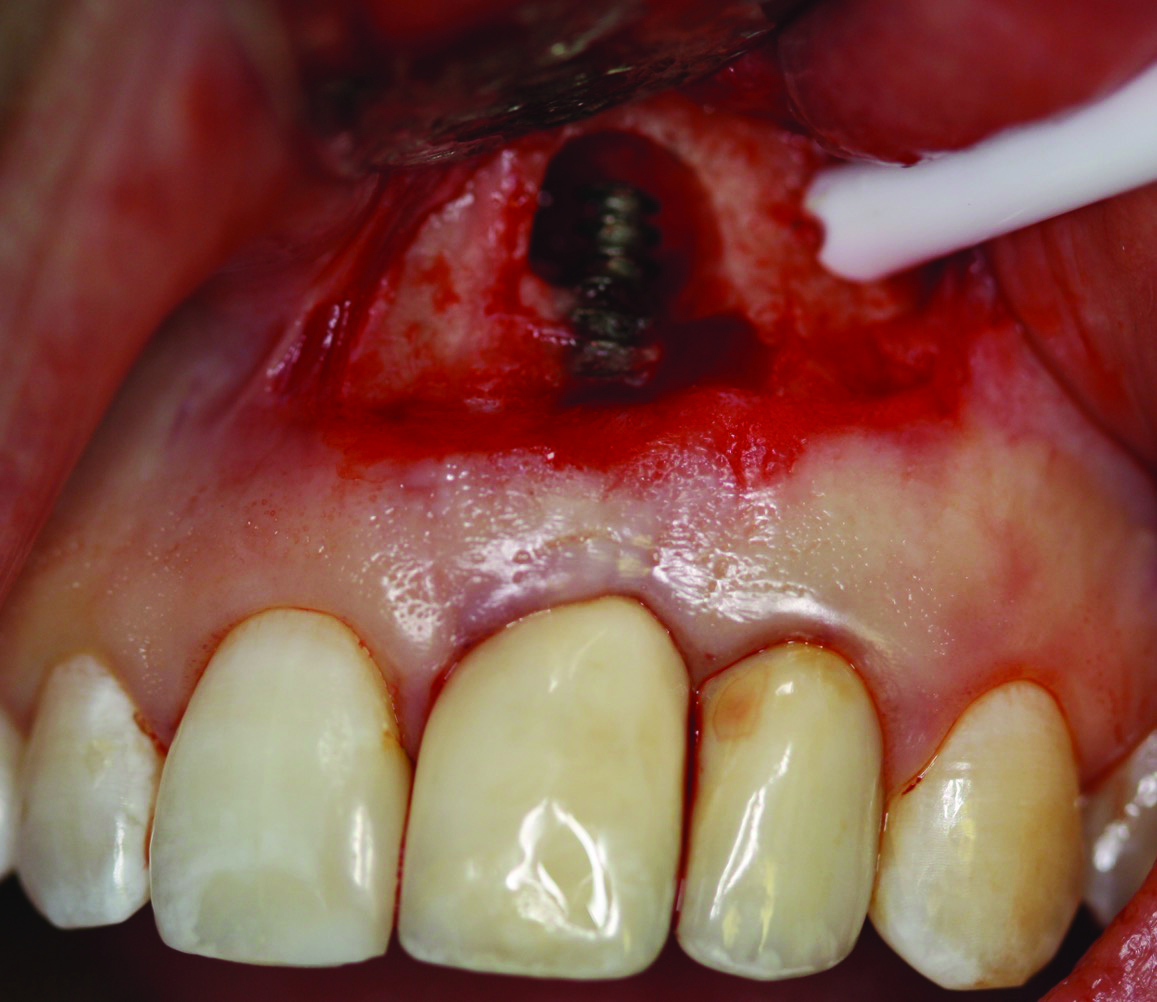

Fig 9. Case 2: Full-thickness flap reflection, extraction of tooth No. 5, debridement and cleaning of implant No. 6 with titanium scalers and titanium brush with doxycycline–saline slurry. Note extensive implant thread exposure approaching the apex. No mobility of the implant was noted.

Figure 9

The patient in case 2 received a crestal incision with full-thickness flap elevation, then tooth No. 5 was extracted (Figure 9). Implant debridement followed the same protocol used in case 1. FDBA was mixed with a small amount of doxycycline and placed around the implant (Figure 10). A resorbable collagen membrane (not pictured) was secured with a tack. Primary closure was achieved with expanded polytetrafluoroethylene (ePTFE) sutures (Figure 11). An immediate post-surgical radiograph showed bone fill and the tack (Figure 12).